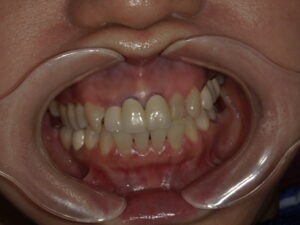

オールセラミッククラウン を セットした 患者さん。

50代 半ば の チャーミングな 女性です。

お越しに なられた 際

こんな 感じ でした。

完成した オールセラミッククラウン修復を セットした の です。